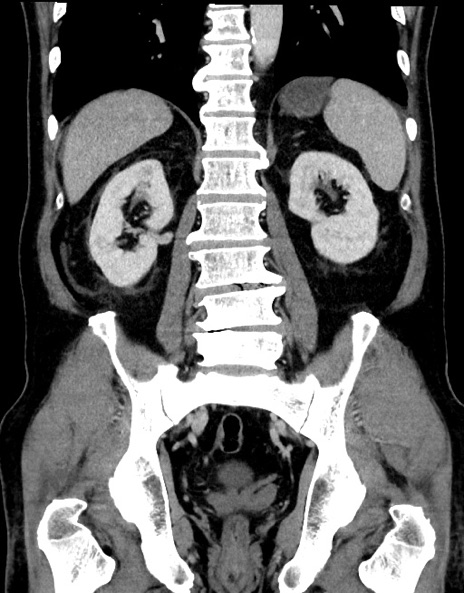

症例15(冠状断像)

【症例】70歳代男性

【主訴】腹痛

【現病歴】今朝から腹痛あり。全体的に痛い。特に左上の方。排ガスが今日はない。冷や汗が出る。

【既往歴】直腸癌術後

【身体所見】左側腹部〜上腹部に圧痛あり。腹膜刺激症状明らかなではない。軽度反跳痛。左下腹部に術後瘢痕あり。

【データ】WBC 7700、CRP 0.02